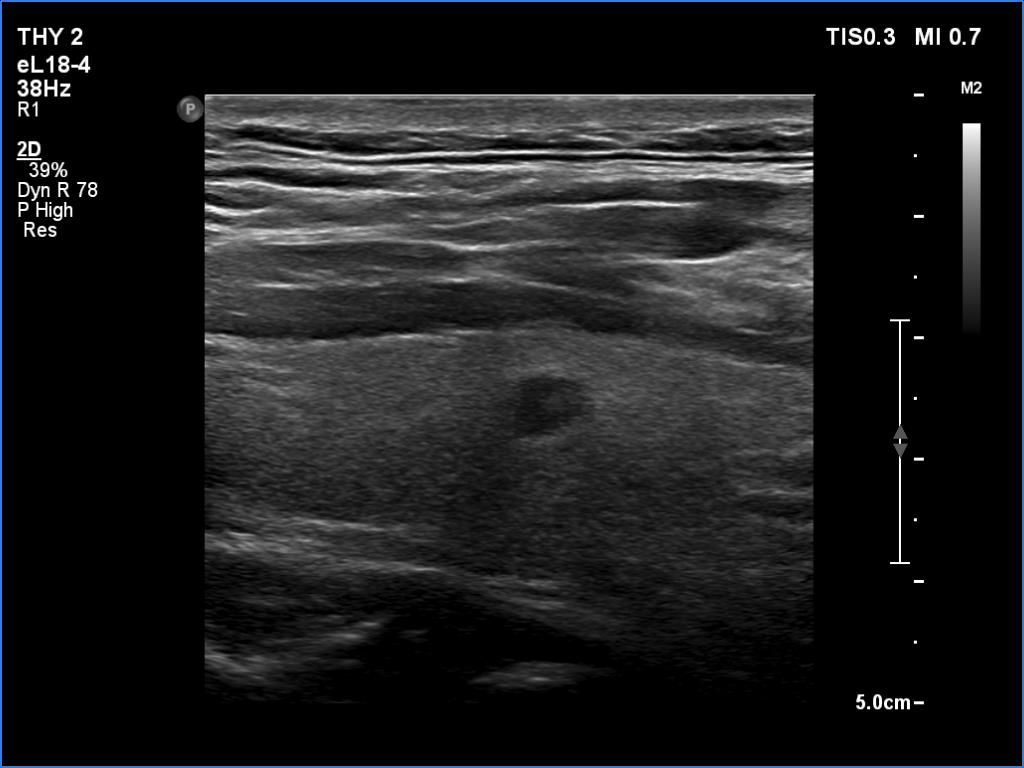

Right lobe, longitudinal scan